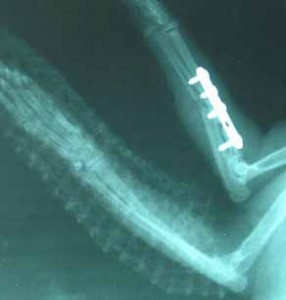

Dne 30.03.2006 se Sisi podrobila operaci, při které byla provedena osteosyntéza, kdy se tato těžká zlomenina fixovala šrouby. Druhou frakturu

fixuje termoplastická dlaha. Sisi se po této těžké operaci velice dobře